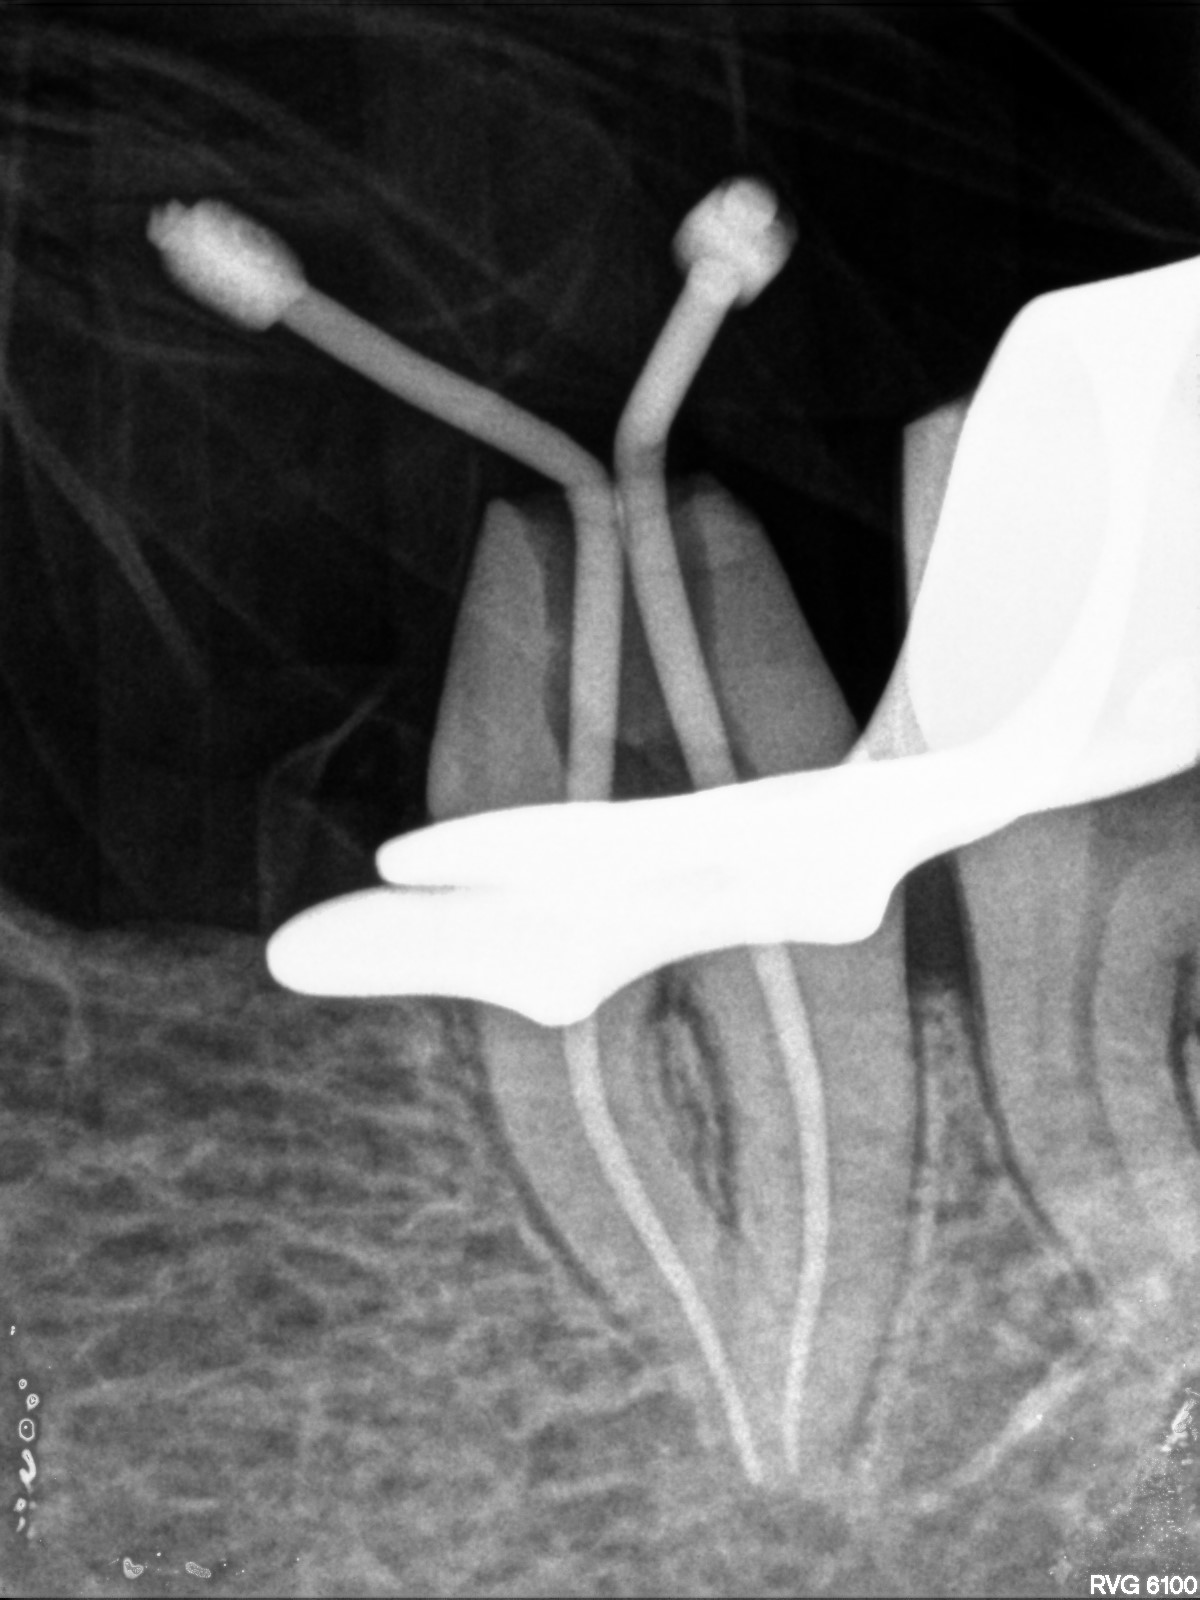

Durante il trattamento

Il trattamento endodontico è ormai veloce grazie alla possibilità di utilizzare strumenti rotanti di ultima generazione e alle moderne apparecchiature a disposizione come il rivelatore apicale che permette all’odontoiatra di stabilire con una certa sicurezza la lunghezza dei vari canali.

Il trattamento endodontico consiste nella rimozione della polpa infiammata ed infetta, e nella sua sostituzione con un’otturazione permanente in guttaperca e cemento canalare, previa adeguata detersione e sagomatura dei canali radicolari con strumenti manuali e rotanti.